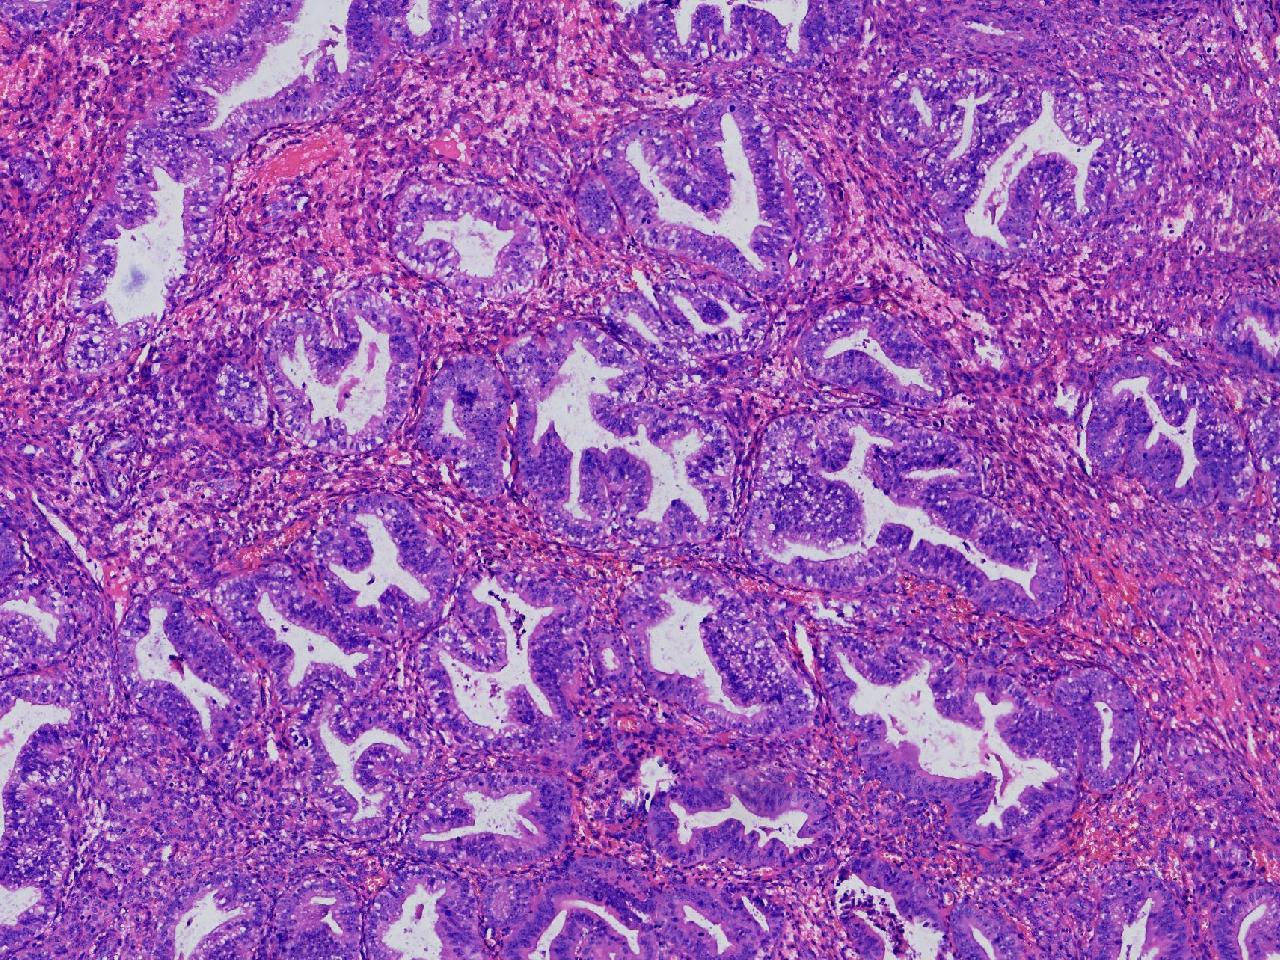

请教。1.有没有非典? 2.内膜是什么变化?

女,50岁,彩超示:粘膜厚度1.1cm。宫腔可见数个高回声,提示宫腔息肉。

子宫内膜+内膜息肉

灰粉色不整形软组织多块,3X3X2厘米。

子宫内膜息肉。

没有非典。

无非典型性子宫内膜增生,子宫内膜息肉

无非典内膜伴息肉。